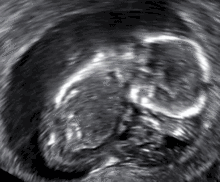

- الإجهاض الصامت: موت الجنين ولكن لم يتم اجهاضه بعد، ويتم اجهاضه في وقت لاحق ويسمى بالإجهاض الصامت.[41][42]